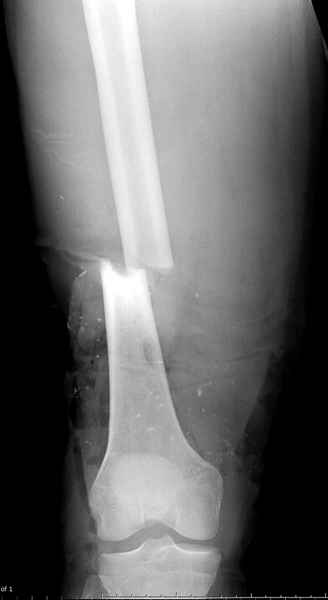

Сегодня выполнена повторная достаточно радикальная хирургическая обработка ран, иссечены участки уже сформировавшихся некрозов на голени. Рана на бедре чистая, отек значительно уменьшился, так же к сожалению, как и количество отломков: часть пришлось удалить из-за полного отсутствия связи с мягкими тканями. Рана бедра закрыта вакуумной повязкой. Общее состояние улучшается. Последующие рентгенограммы обязательно представлю.”

Хирургическую обработку надо повторить неоднократно до очищения раны. Фиксатор типа "бедро-голень" помогает стабилизировать конечность и облегчит обслуживание.

Больному с политравмой установлен наружный "spanning-bridging" фиксатор, после нескольких Irrigation&Debridment на фоне отрицательного посева из раны, через открытый участок установлен 4.5 mm Locking Plate.

На фоне фиксированного перелома бедра мероприятия по восстановлению мягкотканого покрова. Перелом голени зафиксирован после стабилизации бедра традиционным методом.